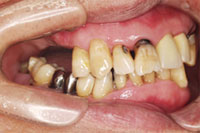

入れ歯で噛めない、他医院で骨がないのでインプラントができないと言われた患者様の症例

口内写真

吉本歯科医院では、口内写真とパノラマレントゲンを撮影し、まずは顎の骨の状態まで詳しく確認しました。

院長の吉本の診断は、次の3つでした。

・入れ歯では合わない、噛めないのは当たり前

・合わない入れ歯を入れているために骨がどんどん退縮していってる

・入れ歯を入れたり入れなかったりするため、歯並びがどんどん崩れだしている